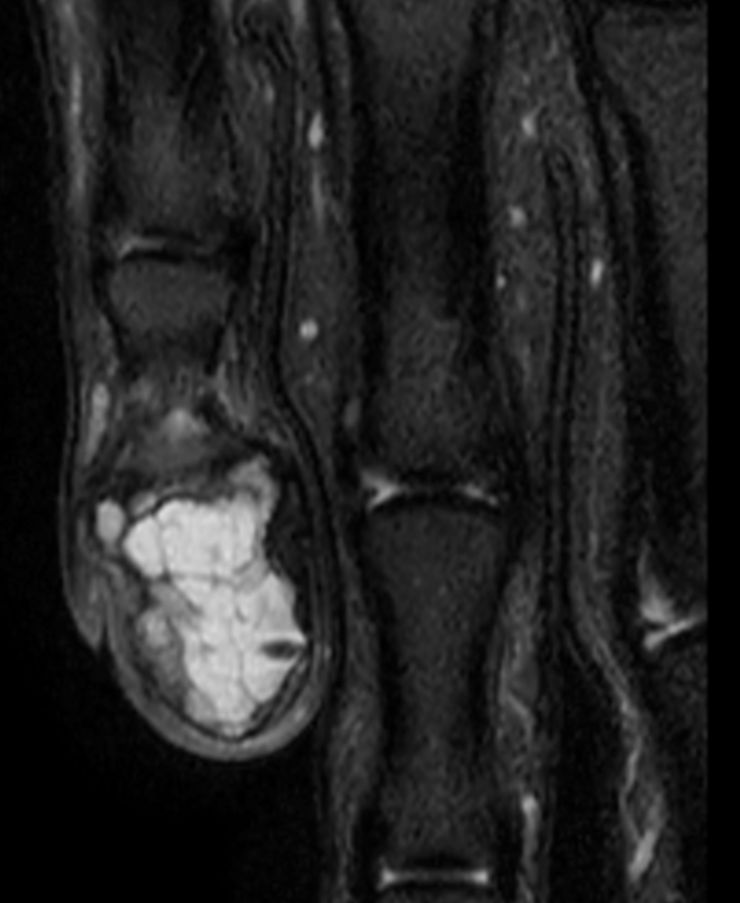

T2w TSE Compressed SENSE